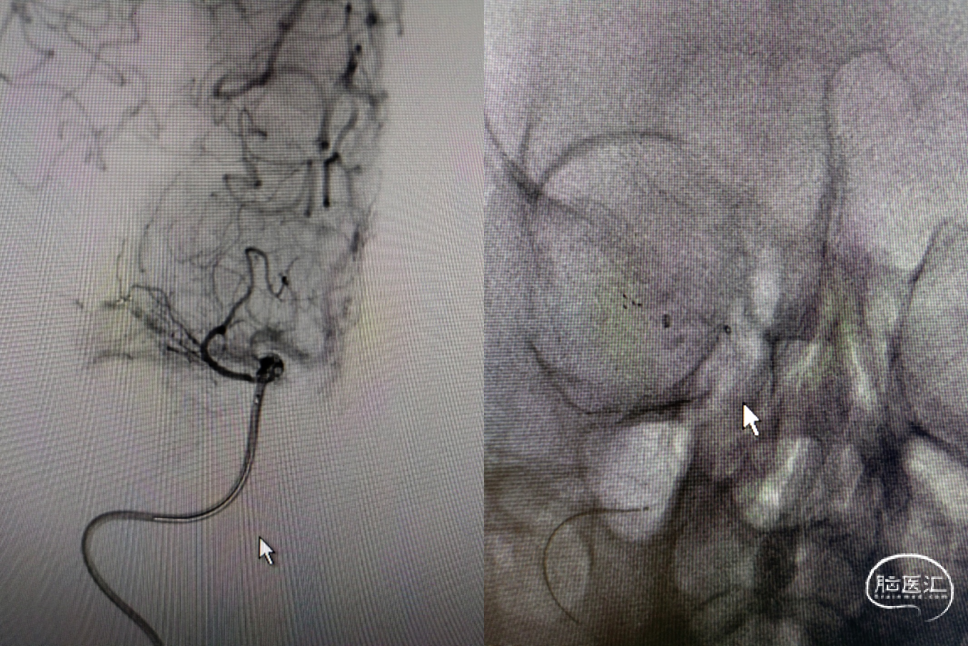

6F-远端通路导管在黑泥鳅导丝的指引下通过闭塞段送至眼动脉段,造影证实闭塞段在海绵窦段,予以ADPAT技术取出少量血栓,仍未开通。

通过微导管释放取栓支架,SWIM取栓技术,可见海绵窦段狭窄,前向血流不稳定。